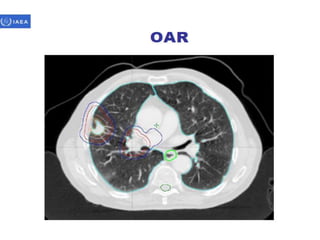

Volume definition

• Prerequisite for 3-D treatment planning.

• ICRU reports50 & 62 define & describe target

& critical structure volumes.

• volumes defined prior to treatment planning

– Gross tumor volume (GTV).

– Clinical target volume (CTV).

• Defined during the treatment planning process

– Planning target volume (PTV).

– Organs at risk.

• As a result of treatment planning, volumes described.

– Treated volume (TV).

– Irradiated volume (IRV).